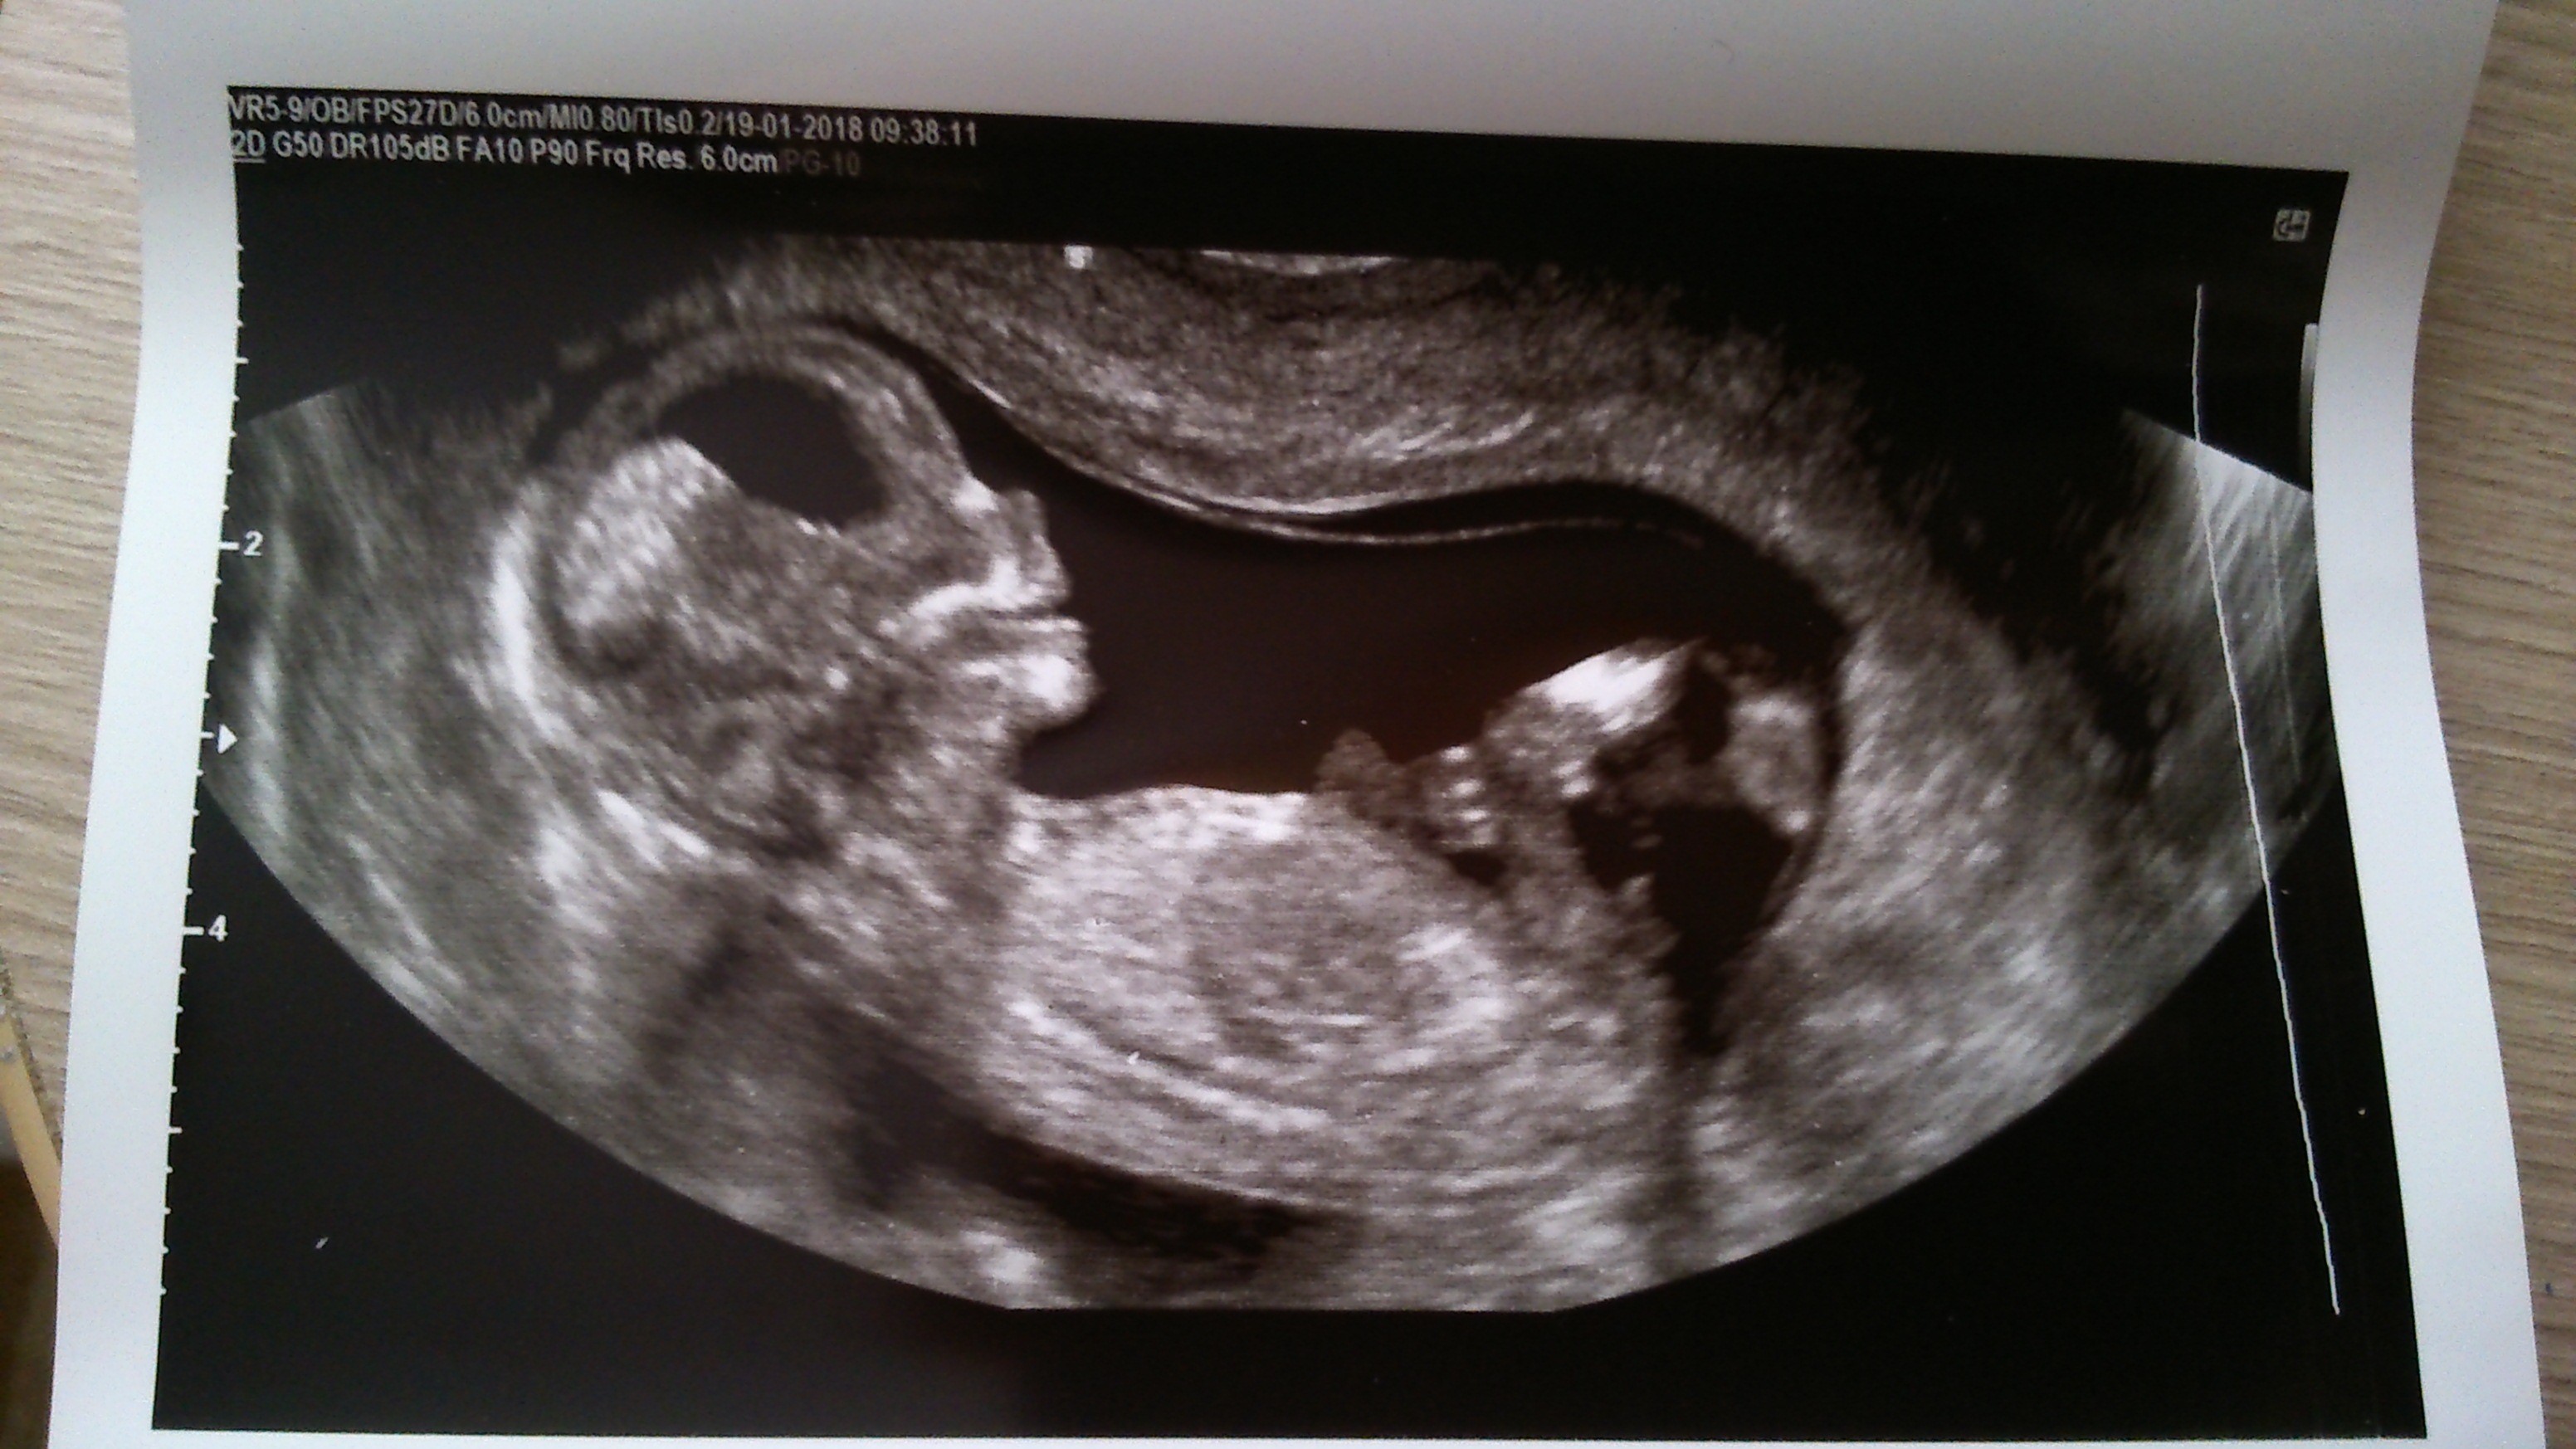

Zobacz załącznik 835955 Zobacz załącznik 835956 Zobacz załącznik 835953 Zobacz załącznik 835954 Ja jestem dopiero po usg prenatalnym, dzidzia ma 7 cm, według usg trochę starsza i termin przesunął się na 25.07. Dziecię w dobrym humorze uśmiechało się aż buzia otwarta była. Niestety nie chciało się pokazać. Na zdjęciu coś widać coś zwisa tylko nie wiem czy ty siusiak czy pepowia, zapomniałam zapytać.